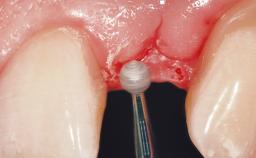

Immediate Flapless Placement of an Implant in a Maxillary Right Lateral Incisor Site

This 43-year-old male patient, a non-smoker, came to our practice because of a fracture of tooth 12 caused by a bicycle accident. Due to the combined para- and infrabony crown and root fracture, tooth extraction, and subsequent implant placement were suggested to the patient as the therapy of choice. The patient had high esthetic expectations with regard to the treatment outcome and asked for an immediate fixed provisional restoration. His individual esthetic risk profile summed up to a medium esthetic risk.

Placement Protocol Immediate implant placement

Tooth Site Maxillary incisor or canine

Socket Morphology Single-root socket